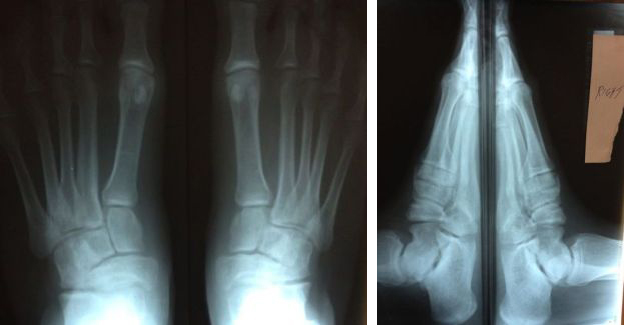

This 21 year old athletic male was born with a clubfoot deformity. He has had soft tissue correction (B/L posterior, medial, lateral, and plantar release) at two years of age. His chief complaint is medial and lateral ankle joint pain. His limbs are equal in length with >10 degrees of dorsiflexion. He has limited active supination. He has a decreased medial arch.

I made new semi-rigid orthotics with 0 degrees of rearfoot varus, a deep 1st metatarsal cut-out, and forefoot valgus extrinsic post of -3 degrees. The orthotics are comfortable and the left foot is now 99% pain-free, but there is no improvement in the right foot. Any suggestions would be helpful as to what corrections in the orthotics are needed to address the painful right foot without affecting the left foot. Also, what type of surgery should be considered to correct his problems?